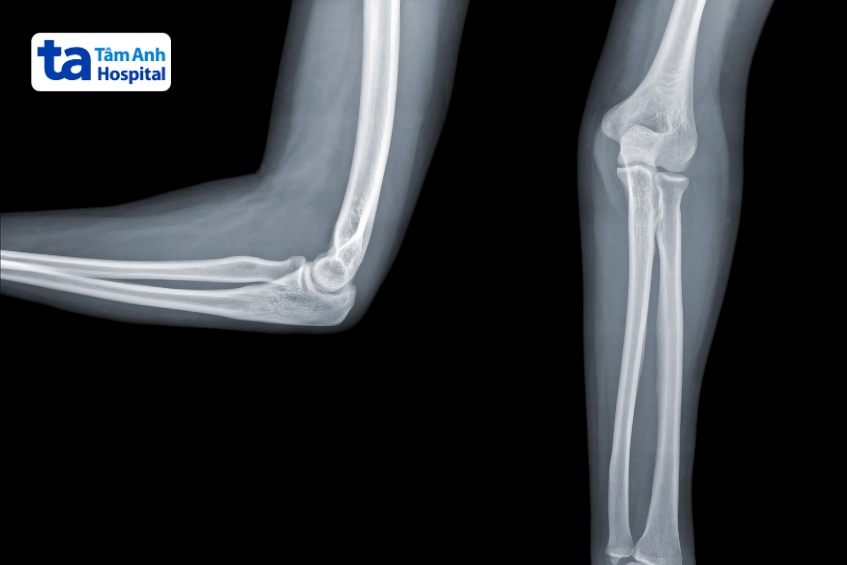

X quang khuỷu tay tư thế thẳng:

X quang khuỷu tay tư thế nghiêng:

Chụp X quang khuỷu tay là kỹ thuật chẩn đoán hình ảnh sử dụng tia bức xạ X để tạo ra hình ảnh cấu trúc bên trong của khuỷu tay. Hình chụp X quang thể hiện khớp khuỷu tay có màu trắng, do canxi trong xương hấp thụ nhiều tia bức xạ hơn so với mô mềm xung quanh. Thông qua hình chụp X quang khuỷu tay, bác sĩ có thể phát hiện và chẩn đoán nguyên nhân gây tổn thương khuỷu tay.

Kết quả từ phim chụp X quang giúp bác sĩ quan sát cấu trúc ở khuỷu tay. Thông qua đó, bác sĩ có thể phát hiện và chẩn đoán tình trạng nứt xương, gãy xương, lệch khớp, u khớp hay các vấn đề khác…